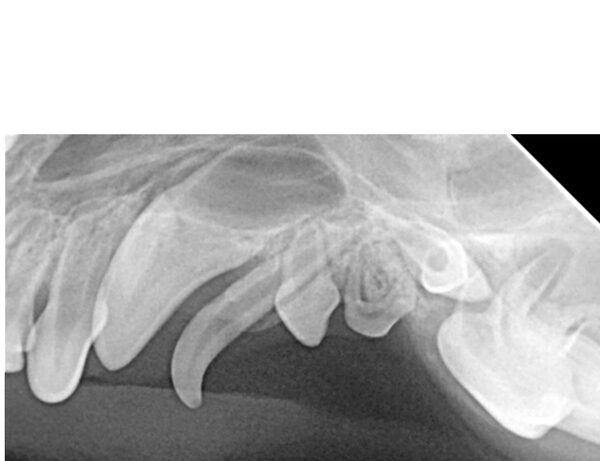

Bei Rex, einem 12 jährigen Mischlingsrüden, fiel starker Mundgeruch auf. Dies ist immer ein Warnsignal, da Tiere Beschwerden mit den Zähnen nicht kommunizieren können. Das Ausmaß des Mundgeruchs korreliert dabei meist mit dem Schweregrad der Zahnerkrankung. Keinesfalls sollte man annemen, dass Mundgeruch bei älteren Tieren normal und unproblematisch ist.

Sein Gebiss wies sehr viel Zahnstein auf und auch eine ausgeprägte Zahnfleischentzündung.

Das wahre Ausmaß zeigte sich allerdings erst nach ausführlicher Untersuchung in Narkose. Das Dentalröntgen und die Sondierung zeigten, dass bereits große Teile des Kieferknochens durch die Parodontitis verursachenden Bakterien zerstört wurde (die gelbe Linie zeigt an, wo der Kieferknochen sien sollte, die rote zeigt an wieviel Knochen bereits zerstört wurde). Dieser Knochenschwund ist leider irreversibel und in diesem Endstadium hilft nur noch die Extraktion.

Parodontitis ist aber nicht nur eine lokale Erkrankung, die zu Schmerzen, Abszessen und Kieferbrüchen führen kann, sondern betrifft den gesamten Körper, da die Bakterien durch das entzündete Zahnfleisch in die Blutbahn übergehen und dadurch in den gesamten Körper streuen.